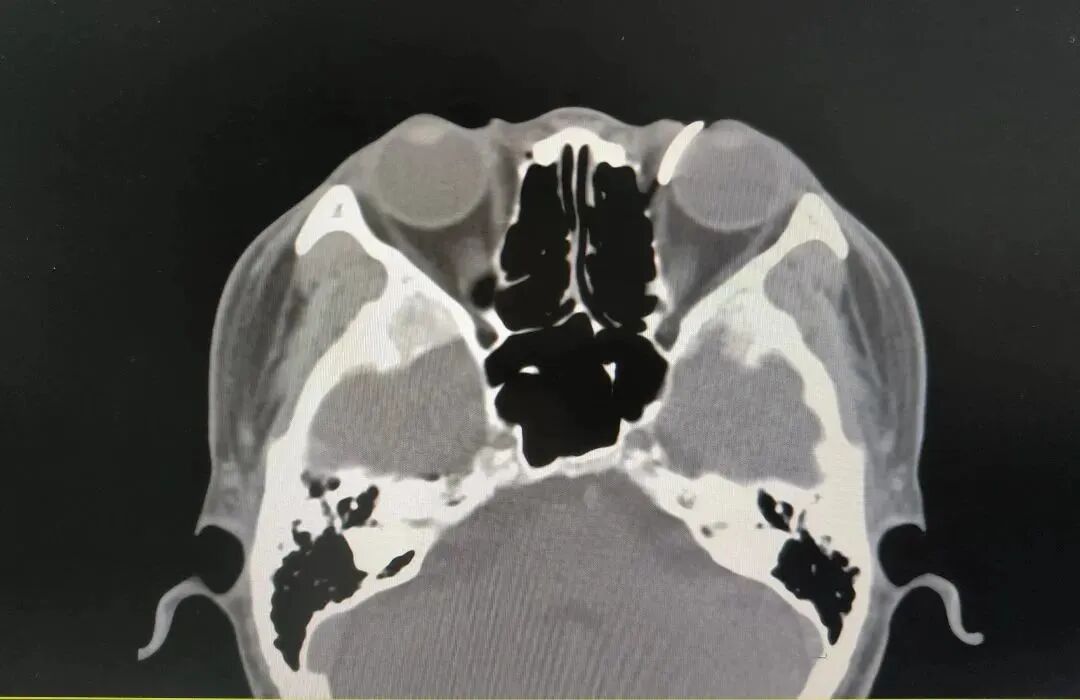

值班医生苏国强第一时间完善眼眶CT及三维重建,初步评估铁钉尚未刺破眼球,但异物较大,三维重建提示异物边缘锐利,贸然取出有造成术中二次损伤的风险。